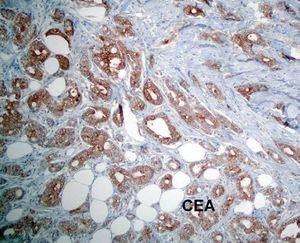

El estudio anatomopatológico de una biopsia realizada en la lesión nodular epigástrica destacó una proliferación celular densa a nivel de la dermis profunda y del tejido celular subcutáneo que respetaba la epidermis y los anejos cutáneos (fig. 2), constituida por células epiteliales dispuestas siguiendo un patrón glandular moderadamente bien diferenciado (fig. 3). Con técnicas de inmunohistoquímica estas células tumorales mostraron una clara positividad para antígeno carcinoembrionario (CEA) (fig. 4) y una negatividad para receptores estrogénicos (fig. 5).

Fig. 4.--Tinciones de inmunohistoquímica que nos ponen de manifiesto una clara positividad para antígeno carcinoembrionario (CEA).